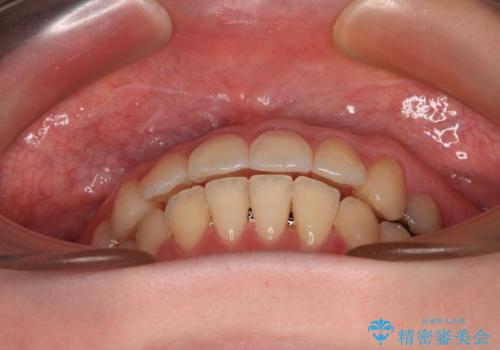

開咬と前方に飛び出した前歯 インビザラインによる矯正治療

- 上下前歯の非接触と叢生を気にして来院された患者様です。

開咬の改善はインビザラインの最も得意とするところであるため、インビザラインを用いて矯正治療を行うこととしました。

舌の突出癖改善のトレーニングをしっかりと行っていただき、上下前歯が接触する咬み合わせを達成することができました。